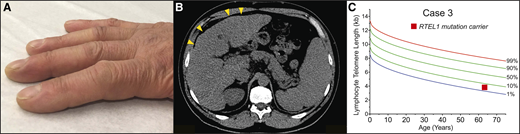

A 62-year-old-man presented to clinic with dyspnea; he had been followed for a history of moderate thrombocytopenia unresponsive to immunosuppression. He had been diagnosed with liver cirrhosis 7 years prior and reported going gray at age 23. His family history was negative for lung or hematologic disease. His physical examination showed an age-appropriate man who was otherwise well but had digital clubbing (Figure 4A). Review of recent imaging showed a nodular liver contour, splenomegaly with evidence of varices (Figure 4B), and incidentally detected lower lobe predominant subpleural reticular opacities and traction bronchiectasis. The constellation of bone marrow failure, liver disease, and early signs of pulmonary fibrosis suggested a short telomere syndrome. The patient’s telomere length fell between the 1st and 10th percentile for age, and genetic testing identified a heterozygous frameshift mutation in RTEL1 (Figure 4C). Pulmonary function tests showed a markedly decreased carbon monoxide diffusion capacity with only a mild restrictive ventilatory defect. Agitated saline echocardiography showed delayed right-to-left shunting indicative of intrapulmonary shunting and supportive of the diagnosis of hepatopulmonary syndrome (HPS). The patient’s immunosuppression was withheld, given the diagnosis of telomere-mediated bone marrow failure, and he is being monitored by a multidisciplinary team for progression of his lung, liver, and marrow disease.

Clubbing and dyspnea can be a presenting feature of telomere-mediated hepatopulmonary syndrome. (A) Image of digital clubbing typically seen. (B) Abdominal CT image showing liver with nodular edges (yellow arrowheads) and secondary splenomegaly due to portal hypertension. (C) The lymphocyte telomere length by flowFISH in older patients with short telomere syndrome presenting over age 60 overlaps with the lower decile of the normal range.